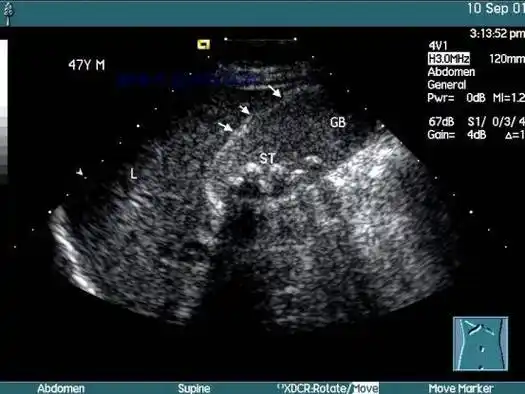

立竿见影精准排雷高危老年胆囊炎患者救治介入超声解难题

全腹部ct检查(图1)①胆囊多发结石伴胆囊炎;胆囊底部见气液平面,胆囊